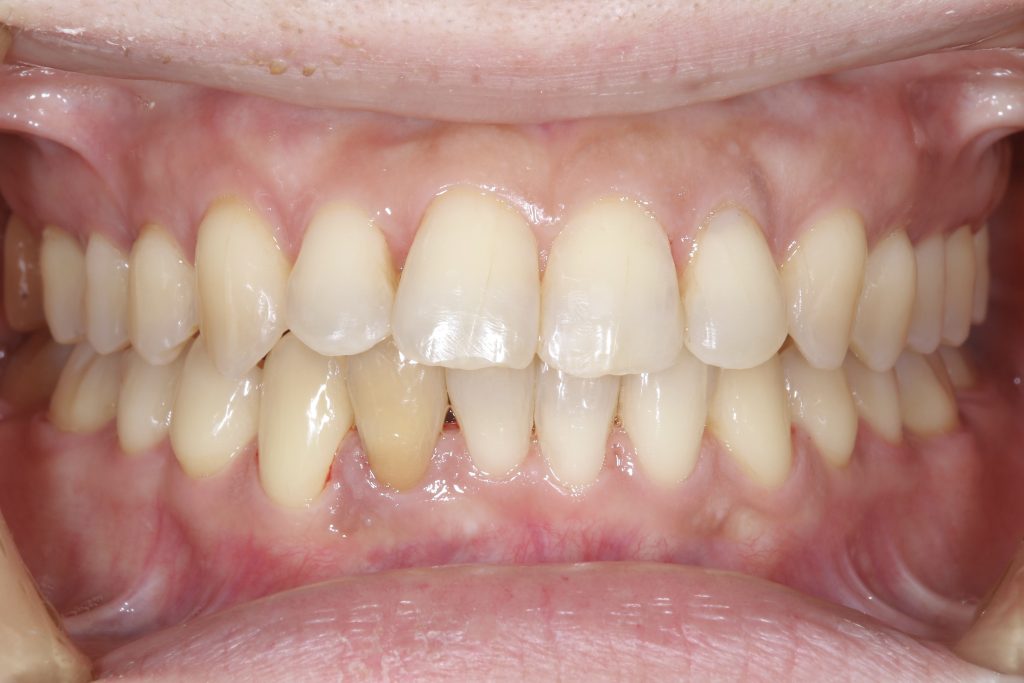

受け口の状態により、上の歯が内側に入り込み、反対の噛み合わせになっている部分が見られました。見た目の問題だけでなく、噛み合わせのバランスにも影響を与えていました。

自信を持って笑えるようになった、その瞬間

治療終了後、整った歯並びに患者様ご自身も思わず感動されたご様子で、

「これでやっと人前でも自信を持って笑えます。やってよかった、本当にそう思います。」というお言葉をいただきました。

- 前歯部交叉咬合を伴う不正咬合

- ゴムメタルワイヤー矯正

- 2024年9月6日(10ヶ月)